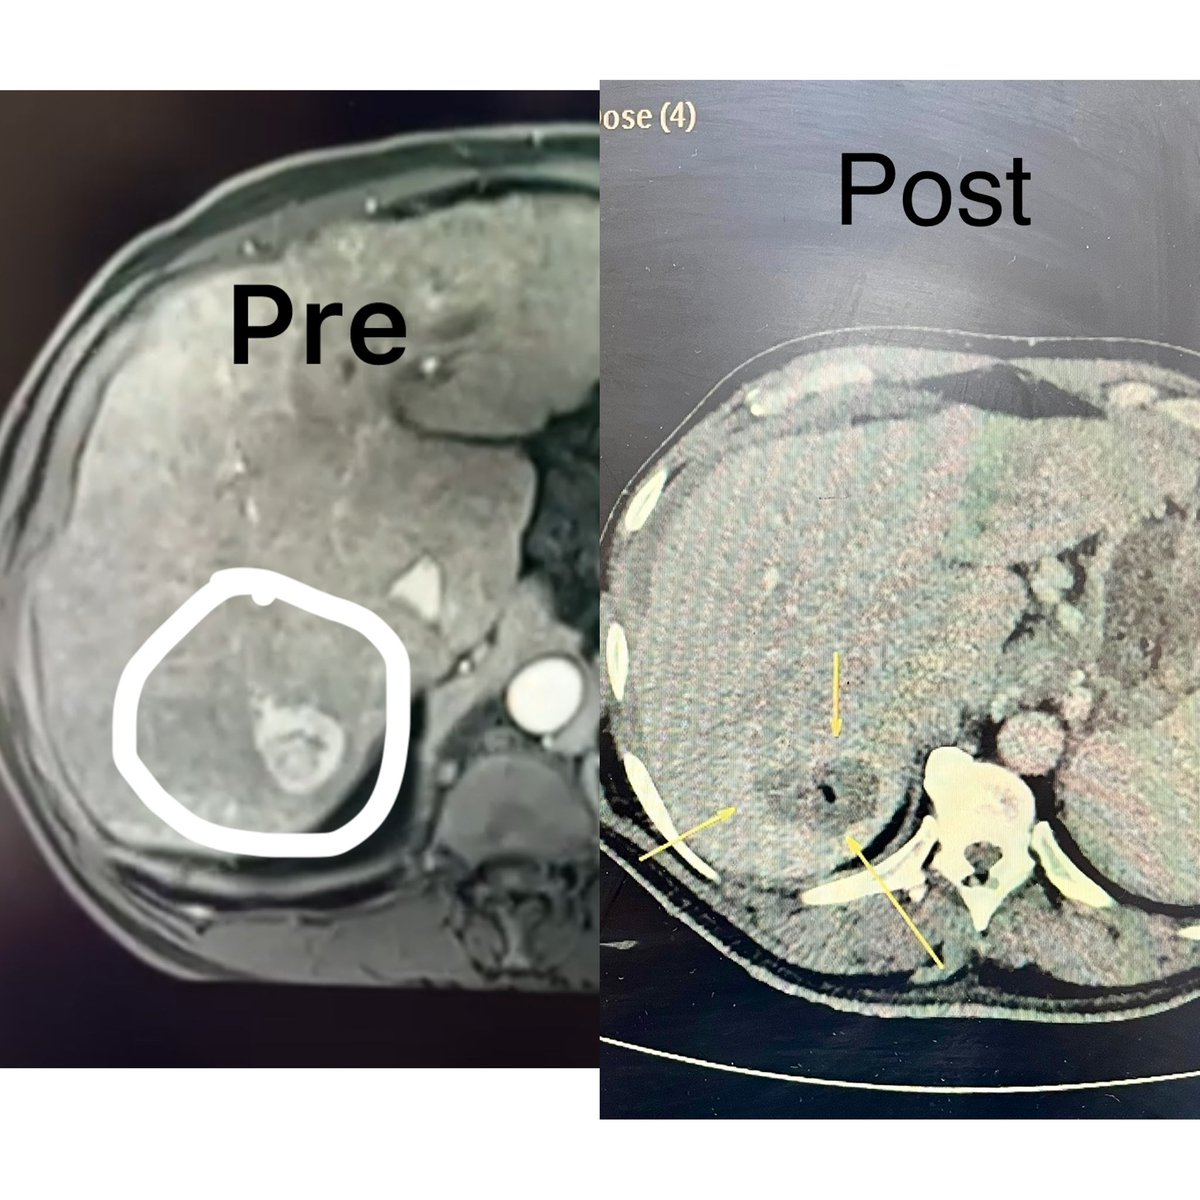

#interventionaloncology 5 - Solitary HCC - #microwave ablation - complete necrosis. Tumor free treatment in 5 minutes - most minimal invasive way of curing the HCC. Asian Hospital ISVIR India #interventionalradiology

#interventionaloncology 5 - Solitary HCC - #microwave ablation - complete necrosis. Tumor free treatment in 5 minutes - most minimal invasive way of curing the HCC. <a href="/AIMSFaridabad/">Asian Hospital</a> <a href="/ISVIRIndia/">ISVIR India</a> #interventionalradiology